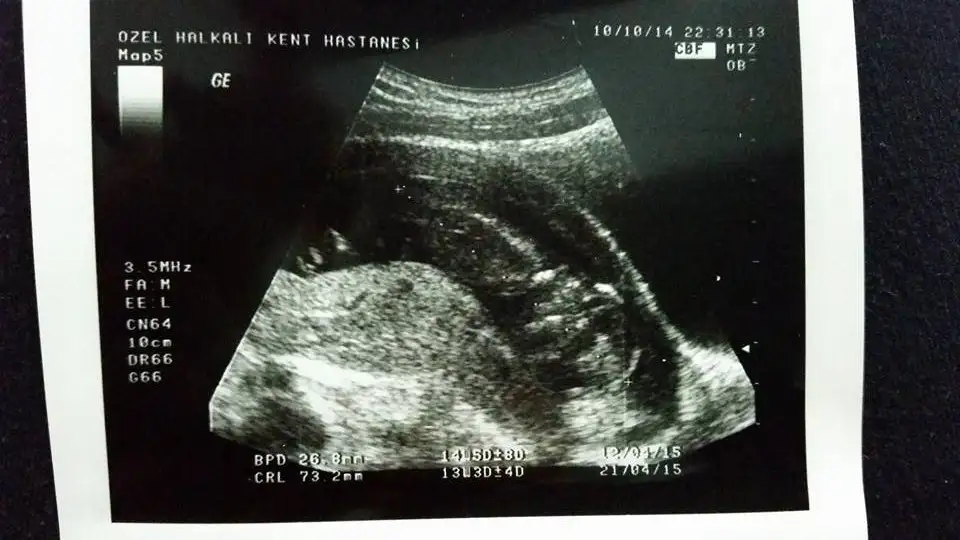

Size yorum yaptimmi bilmiyorum ama kız olabilir bebisiniz bazı arkafaslarinki gorunmuyo resimleri telden giriyorum oyuzden acmiyo fotolarKizlar benim onceki gonderime sagolsun hcan86 arkadas yorum yapti ama bu isi anlayabilen diger arkadaslarda yorum yapabilirler mi acaba?

Anladigim kadariyla bana kiz gibi geldi.Bana da yorum

Kızlar ne olur bana bi yorum yapın ya herkese yaptınız bi bana yapmadınızAnladigim kadariyla bana kiz gibi geldi.

Goruntuler pek net degil yani nub cikintisini goremedimKızlar ne olur bana bi yorum yapın ya herkese yaptınız bi bana yapmadınız